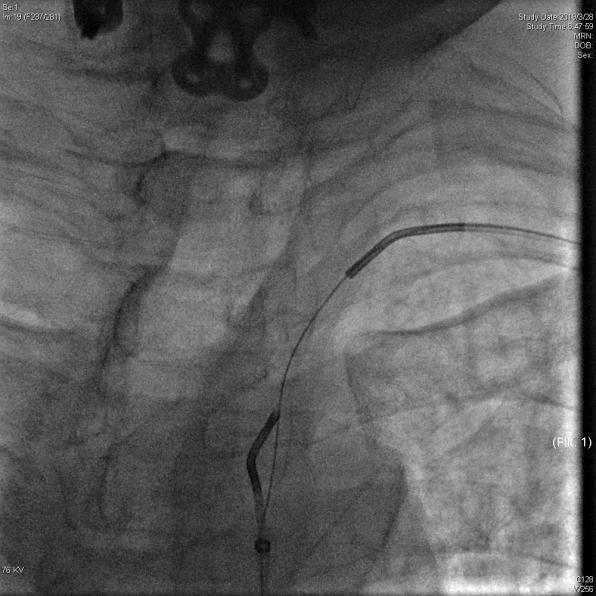

图3 双向会师建立通路                             图4 植入支架后血流恢复通畅